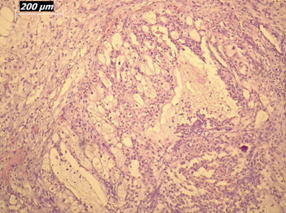

Renal artery embolization was performed under local anesthesia using the Seldinger technique, with complete occlusion confirmed angiographically (Figures 3-4). Six days later, a transabdominal left radical nephrectomy was performed. Intraoperatively, the kidney appeared markedly enlarged and deformed, containing cystic and soft-tissue components but without invasion of adjacent structures (Figures 5-6). The operation was uneventful, with minimal blood loss (approximately 300 mL) and no transfusion requirement. The postoperative course was smooth, and the patient was discharged on postoperative day five in good condition. Histopathological examination revealed that the upper pole lesion corresponded to a low-grade clear cell RCC with focal necrosis (Figures 7-8). The larger lesion was identified as a well-differentiated liposarcoma (Figures 9-10), correcting the initial radiologic misdiagnosis of angiomyolipoma. At the three-month follow-up, the patient remained asymptomatic. Laboratory results indicated mild renal impairment (creatinine 169 µmol/L, urea 9.2 mmol/L) but normal inflammatory markers. Ultrasonography revealed no recurrence or lymphadenopathy. Nephrology follow-up was continued due to reduced renal function. Six months postoperatively, CT imaging of the thorax, abdomen, and pelvis demonstrated no evidence of local recurrence or distant metastasis. Given the absence of standardized surveillance protocols for synchronous RCC and WDLPS, followup was conducted in accordance with conventional RCC and retroperitoneal sarcoma guidelines.

Figure 10: Higher-magnification view (20×) of liposarcoma showing mature adipocytes and minimal atypia.